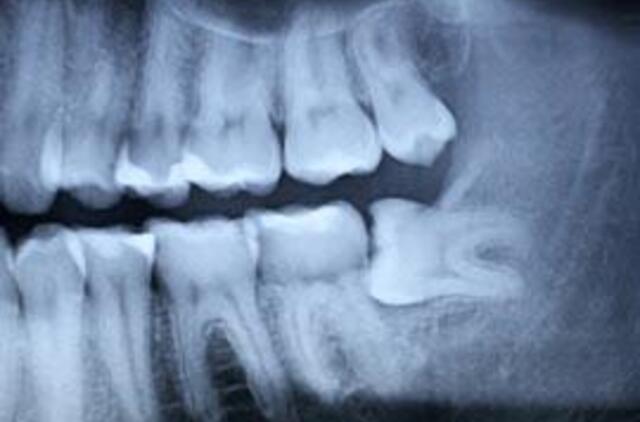

Šešiolikmetei paauglei iš Sicilijos dantys nebetelpa burnoje. Iš karto išdygus 33 nereikalingiems dantims paauglė operuota Italijos Riminio miesto klinikoje.

Paauglė kenčia nuo retos formos displazijos - kai kurių organizmo dalių, organų ar audinių formavimosi sutrikimų.

Italijos klinikos medikai atliko mergaitei

sudėtingą operaciją - pašalino šešis nereikalingus dantis. "Situacija labai neįprasta, nes ši liga tik vienu atveju iš milijono gali sukelti nereikalingų dantų augimą, o mes dar nebuvo matę, kad išaugtų tiek daug nereikalingų dantų", - sakė daktaras Mauras Merlis (Mauro Merli).

Gydytojai dantis mergaitei šalina jau aštuonerius metus, nuo 2001-ųjų, per tą laiką jai ištraukė 21 dantį. Po kelių mėnesių mergaitei bus atlikta paskutinioji operacija, kurios metu medikai turi pašalinti likusiuosius šešis nereikalingus dantis. Tik po to pacientei liks tinkamas jos amžiui dantų skaičius, rašo "RIA Novosti".